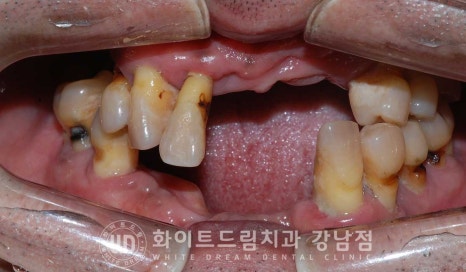

오늘 소개해 드릴 환자분도 치아가 한두 개 빠질 때는 별 대수롭지 않게 생각하시다

다수의 치아를 상실하고 나서야 심각성을 인지하시고

저희 강남화이트드림치과를 찾아오시게 된 환자분이십니다.

환자분의 초진 구내 사진을 보면 남아있는 치아들의 상태는 물론

잇몸의 상태도 굉장히 좋지 못한 상황입니다.

만성 치주염과 대합치 상실로 대부분의 치아가 흔들리고 정출되어 있으며

그나마 남아있는 어금니들은 이미 쓰러진 상태로

살릴 수 있는 치아는 하나도 없는 상태입니다.